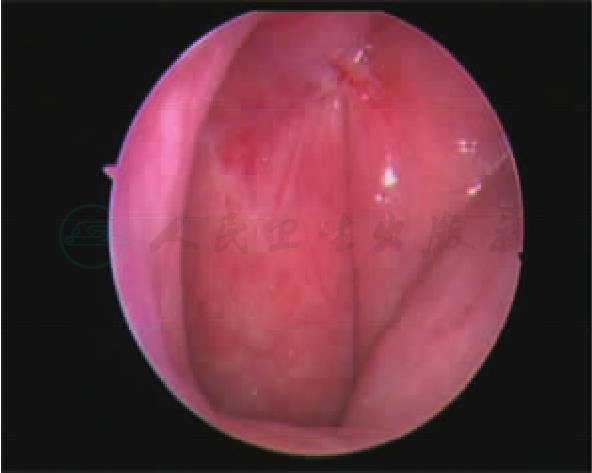

初步分析:考虑鼻咽癌可能性大。患者为中年男性,广东人,临床检查可见鼻咽部左侧隐窝处结节状肿物(图1),血清学检查示EB病毒抗体阳性;患者就诊当地医院,已经行鼻咽病理活检,病理结果初步考虑为“鼻咽癌低分化鳞癌”。

图1 治疗前内镜下鼻咽图片:左侧咽隐窝、后壁可见软组织肿物

目前患者放疗后已经半年,未见鼻咽复发,鼻内镜见鼻咽各壁光滑,未见肿瘤;复查磁共振提示脑膜瘤术野内亦未见复发。

图3 放疗后内镜下鼻咽图片:鼻咽部光滑,左侧隐窝、后壁消失